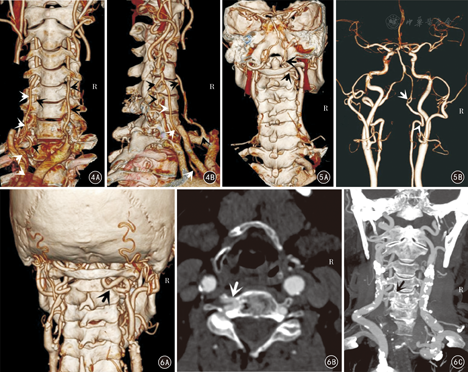

VA的变异包括管径发育细小(图1,图2,图3)、起源部位变异(图2、图4)、各节段行程变异(图2,图3,图4,图5,图6,图7)、数目变异(图4)、分支和异常吻合变异(图5)等。单一变异以一侧VA发育细小或狭窄形成两侧VA不对称最为多见,有66例(33.0%),其中右侧VA细小形成的左侧优势型VA 42例(右VA管径小于3 mm者31例),左侧VA细小形成的右侧优势型VA 24例(左VA管径小于3 mm者19例)。19例MCV中,有12例系由双侧细小的VA(图1)或一侧细小VA合并其他类型变异形成(图2、图3)。

本组有28例(14.0%)30条VA共34个部位表现为不同节段的多种行程变异,如双侧VA分别经不同水平的颈椎横突孔上行入颅(图2、图4、图7);或出C2横突孔后未经过C1横突孔,直接经C1和C2后侧椎弓间进入椎管,形成所谓"C2节段性VA"(图5、图6);或行程中出现折曲向下位椎体内疝入形成椎体动脉环(图6);或出C1横突孔后向C1侧块嵌入,经完整或不完整的骨桥内入颅(图3)等。其中15例(7.5%)行程变异合并其他类型和部位的变异表现为MCV,其中6例(3.0%)同时存在2个部位的行程变异(表2),是最常见的MCV组成类型。

VA起源变异是指VA一侧或双侧起自除同侧锁骨下动脉以外的动脉分支,较常见的是直接起自主动脉,同时多伴有行程的变异(图2、图4)。本组有5例(2.5%,5/200)左侧VA起自主动脉弓,均伴行程变异等表现为MCV。见表2。

文献报道,VA存在起源、行程、数目、异常吻合等多种解剖变异[1,2,3,4,5,6,7,8,9,10],且一种VA变异常合并其他类型的变异[2,3,5,11,12],但缺少深入研究。本组19例(9.5%,19/200)患者存在MCV,同时发现一些常见的MCV表现形式,如起源变异常伴有行程变异,行程变异常在双侧或不同部位同时发生,管腔细小常伴有其他多种变异等。19例MCV中,有6例存在3种以上变异,如本组有1例左VA起自主动脉弓,穿C4~1横突孔入颅,同时右侧VA在C5/6横突之间形成明显前方折曲;另1例左侧双VA分别起自左锁骨下动脉和主动脉弓,在C4/5横突间汇合,同时右侧VA穿C4~1横突孔入颅;均表现特殊复杂,较为罕见。人群中应该存在更为复杂多样的变异表现[7,11,12]。本组观测结果提示,临床医生不仅要注意VA变异的高发生率和多样性,同时要注意在同一患者的多发性和多样性,避免漏诊和手术中的意外损伤。

该变异的发生率为5%~16.2%[3,5,6,9]。由于缺少横突孔的保护或异常折曲也是后循环缺血的重要诱发因素之一[1,4,8]。本组中1例患者临床表现为近5年反复发作的晨起后严重头晕、恶心,自觉天旋地转等小脑缺血症状,0.5~2 d后症状缓解,无其他异常,经多次颅脑平扫CT检查未发现问题,CTA示右侧VA经C7~1横突上行入颅,且VA在C7横突部折曲,其他头颈部血管显示正常。根据CTA可较好解析其发病症状,预计随着年龄的增加,主动脉迂曲加重右侧VA折曲,临床发病可能加重。另一方面,本组统计发现VA行程变异常发生在双侧VA或多个部位表现为MCV,这种多发的变异显然更易于引起临床症状与不适,并且也增加了手中损伤的危险性。

如认识C2节段VA、下颈椎椎体环、寰椎骨桥下穿行等变异,对在环枕融合术、椎体切除/融合术、椎间盘手术和其他多种颈部手术中避免医源性损伤也非常重要[4,5,6,7,8,9,10,11,12,13]。有研究建议把CTA作为术前了解VA变异情况、确定治疗方案的重要检查方法[3,4,9]。经皮穿刺颈椎间盘介入手术在临床开展已有多年,本文中1例患者左侧VA向C4椎体内折曲疝入,形成椎体动脉环,变异发生在该类手术常见的穿刺部位,在不知道存在该变异的情况下穿刺显然非常危险。